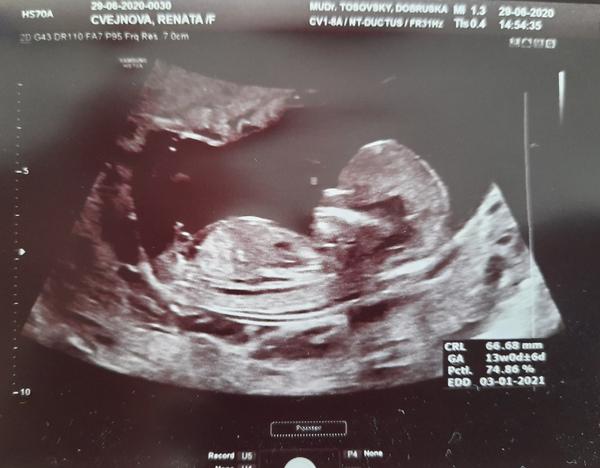

Foto z ultrazvuku. Holčička nebo klučík?

Hezký večer, dnes jsme byli na screeningu v prvním trimestru, paní doktorka nám řekla pohlaví s jistotou 90%, nicméně prý už se takhle jednou sekla, tak by mě, čistě ze zvědavosti, zajímalo, co myslíte vy? Mě to podle toho co jsem na internetu vyčetla sedí s paní doktorkou, ale víte jak, sem baba zvědavá 🙂

takhle to poznala i doktorka, pak mrkla zespodu mezi nožky a ještě si to jakoby potvrdila, ale v 1.trimestru se to poznává právě podle fotky z profilu 🙂

tak paní doktorka říkala, že to bude na těch 90% holčička